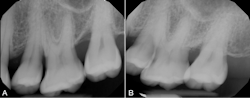

Periodontal ligament stem cells (PDLSC), located within the periodontal ligament, are of particular interest as these progenitor cells are involved in the processes of repairing alveolar bone and periodontal tissues that surround teeth. Specifically, exosomes derived from these cells (periosomes) may be the promising exosome of choice for treating gum disease. Exosomes for periodontitis (termed periosomes) have already been utilized in humans, and the results have been promising. The authors of this article have been among the first groups to investigate periosomes for bone regeneration in patients (figure 1). Periosomes exhibit essential roles in biological mechanisms, including the stimulation of cellular proliferation, angiogenesis promotion, and the enhancement of tissue repair capabilities.2

The case in Figure 1 presents a patient who was losing significant bone around a back molar. The after photo represents a new radiograph taken six months later, displaying new bone regeneration using periosomes. Stay tuned for upcoming publications from Dr. Froum and Dr. Estrin on the use of exosomes in humans.